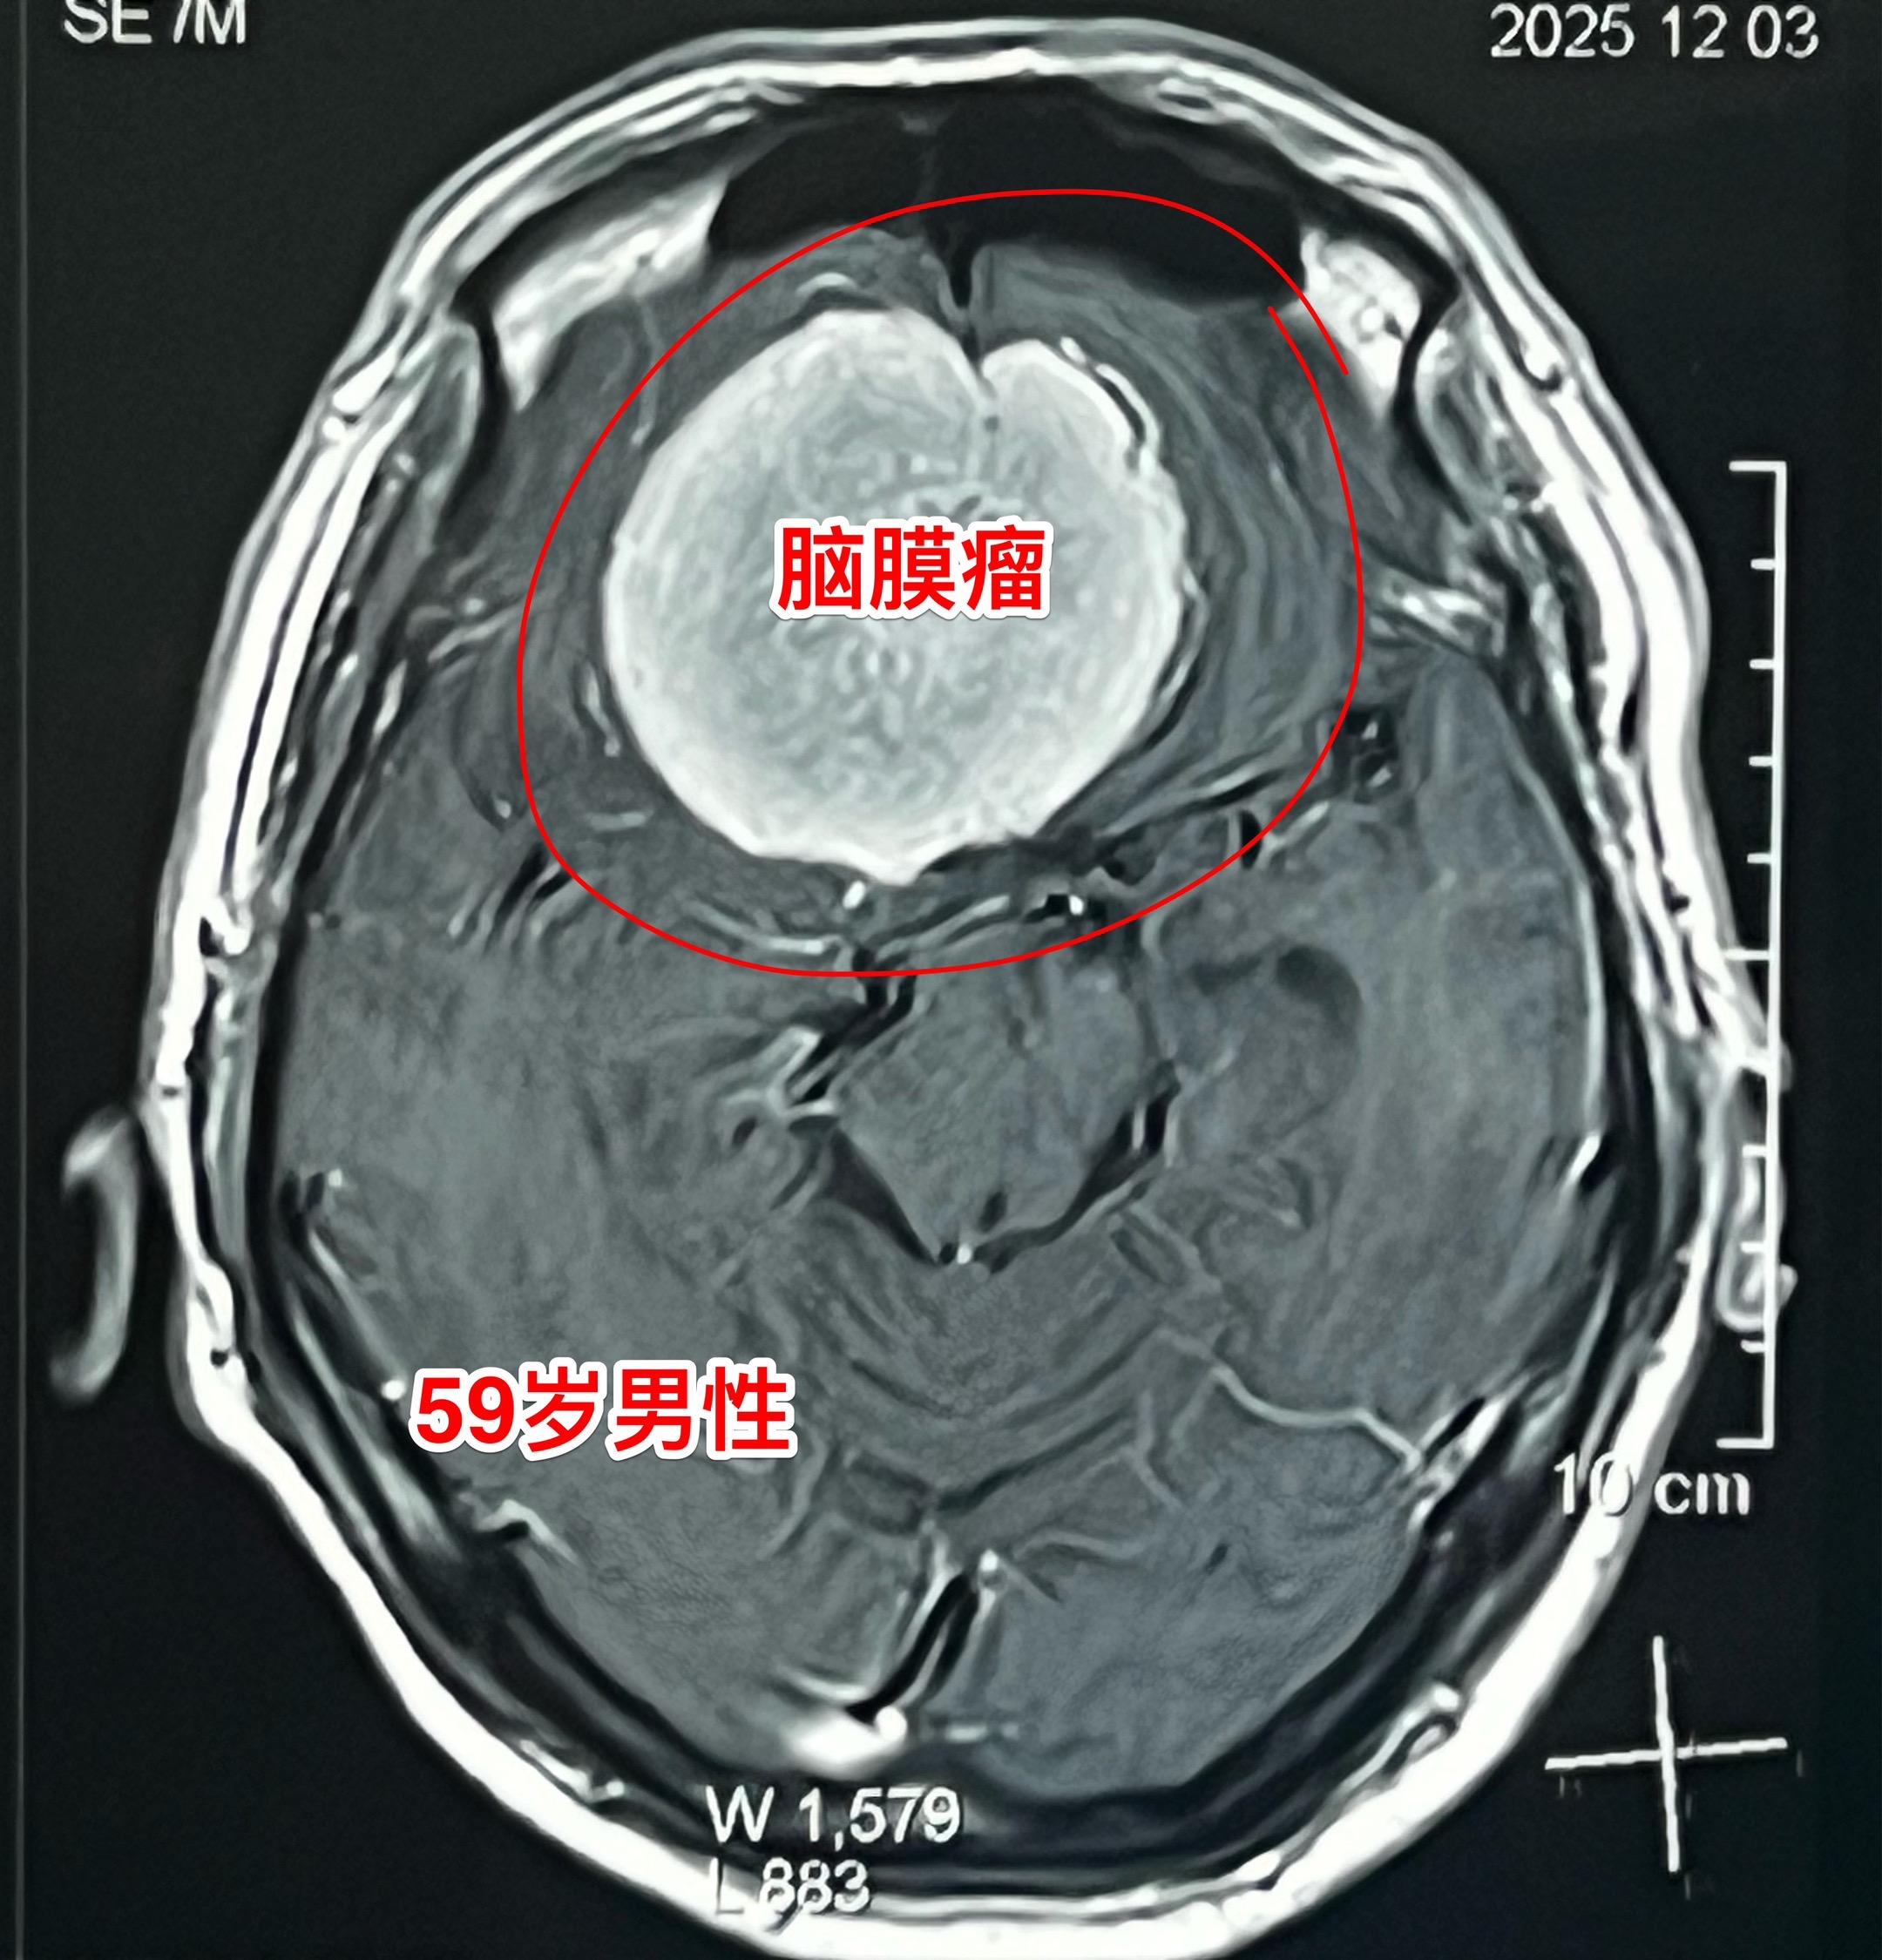

脑膜瘤长在不同的部位产生的症状也不同!这个59岁的内蒙古男性,最开始的症状是右眼视力下降,他认为与糖尿病有关,没有作详细检查。今年出现头痛症状,后来又出现左腿无力症状,他自认为是脑梗塞。症状越来越严重,还发现了嗅觉丧失症状。医生建议行脑部磁共振检查,作了磁共振之后就发现了这个巨大肿瘤。 这个脑膜瘤位置靠近嗅神经、视神经,所以导致视力下降和嗅觉丧失,同时肿瘤导致右侧大面积的脑水肿,造成左腿无力。手术后这些症状有望好转。